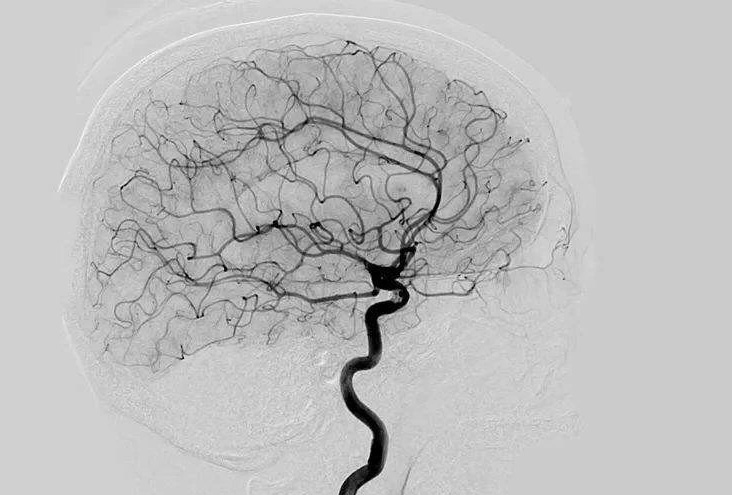

Digital Subtraction Angiography 血管造影机应注意什么?

Digital Subtraction Angiography 血管造影机又称数字减影血管造影机,是通过电子计算机进行辅助成像的血管造影方法,应用计算机程序进行两次成像完成的。在注人造影剂之前,第一次成像工作,图像转成数字信号储存,注人造影剂后,再次成像并转换成数字信号,两次数字相减,消除相同的信号,得到只有造影剂的血管图像。临床主要应用于冠心病、心律失常、瓣膜病和先天性心脏病的诊断和治疗。

数字减影血管造影对脑血管病的诊断方法,创伤性的检查, 脑血管不能是首选或者平时常规检查,需要掌握好适应证和禁忌证,并做好有关准备工作。